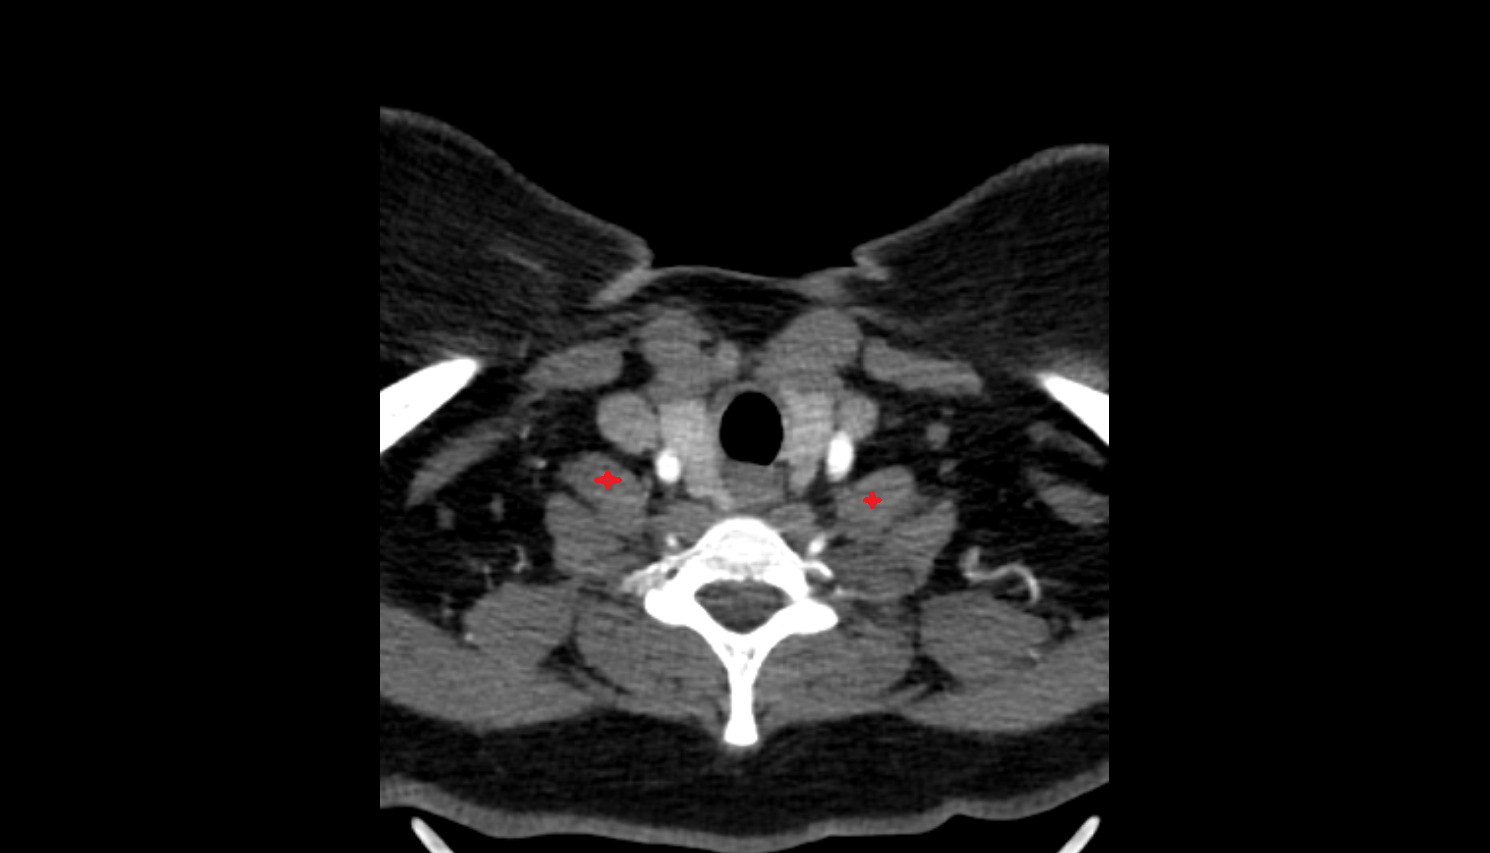

- Carotid bifurcation

- Common carotid artery

- External carotid artery

- Internal carotid artery (cervical part)